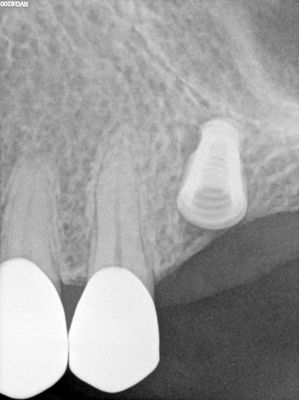

straightforward implant placement with densah drills used at apical end. no entry into sinus chamber, dense bone, had talked about doing a sinus lift but is best to reduce length of procedure.